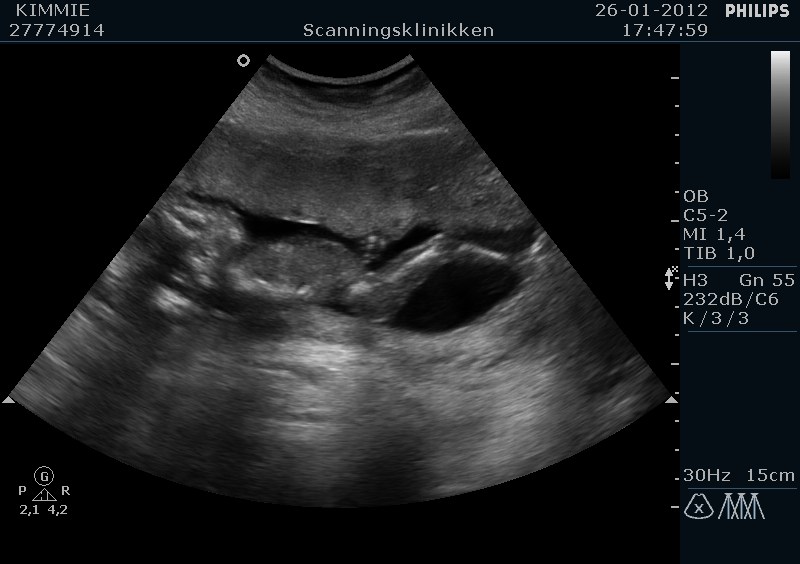

Jeg havde en tyk moderkage som lå ud mod maven og derfor var babs godt gemt, så det tog lidt ekstra tid for at 100 % at kunne identificere kønnet.

Men den er god nok, vi venter en lille....... PIGE mere...

Til sidst lige et par billeder

Vedhæftede fotos (klik for at se i fuld størrelse)